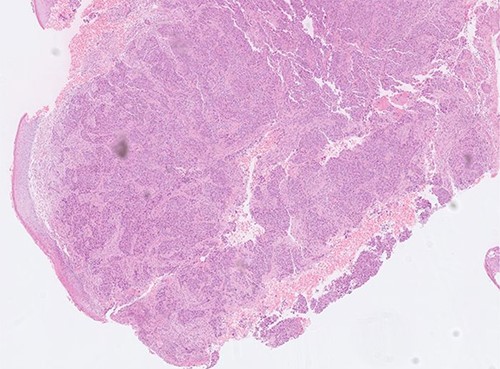

Superficial skin debridement and wound closure was done. The knee aspirate did not grow any organisms after extended cultures. The tissue samples have grown pseudomonas sensitive to piperacillin and gentamicin. She was commenced on 100 mg piperacillin intravenously every 8 hours and one dose of 160 mg of gentamicin after consulting with the microbiologist and checking the renal function. The histopathology showed poorly differentiated adenocarcinoma with sheets and nests of malignant cells and central tumour necrosis, Fig. 3. Immuno-histochemistry showed that tumour was strongly positive for CK5/6, AE1/AE3, CDX2 and CK7 which is suggestive of a metastatic poorly differentiated breast carcinoma, Fig. 4.

Histopathology slide showing poorly differentiated adenocarcinoma with sheets and nests of malignant cells.